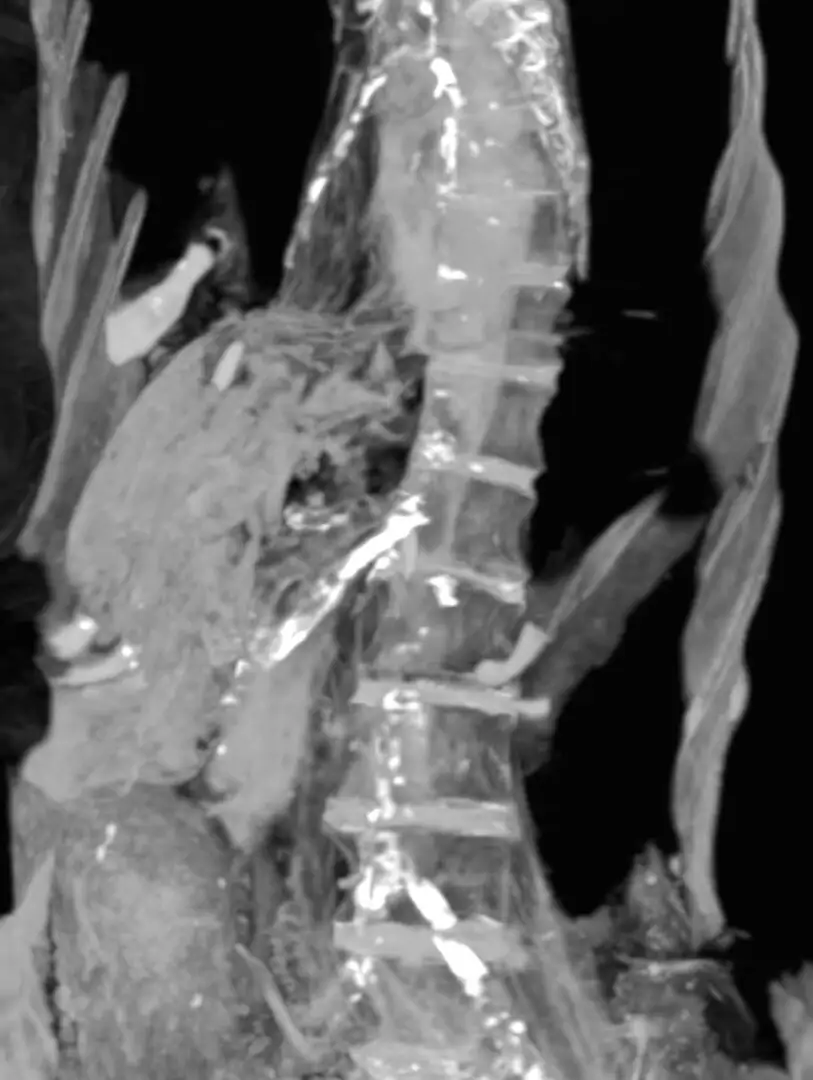

وتوضح نتائج تصوير الأشعة المقطعية التي أجراها خبير الآثار الدكتور زاهي حواس والدكتورة سحر سليم، إلى أن المومياء تعود لسيدة ماتت في العقد السادس من العمر وأن جثمانها (وعلى العكس من بنتاؤر) قد نال عناية بالغة من المحنطين الذين أزالوا الأحشاء ووضعوا مواد باهظة الثمن مثل الراتنج والحنوط المعطرة في تجويف الجسم واستخدموا الكتان الطاهر في لف المومياء.

وذكرت نتائج التصوير المقطعي المحوسب أن “مومياء المرأة غير المعروفة إيه” كانت مصابة بمرض تصلب الشرايين شديد الدرجة، والذي أصاب العديد من شرايين الجسد.

وتفترض الدراسة أن جلطة الأوعية التاجية لـ “مومياء المرأة غير المعروفه إيه” سببت تلف عضلة القلب، مما أدى إلى موتها الفجائي بنوبة قلبية.